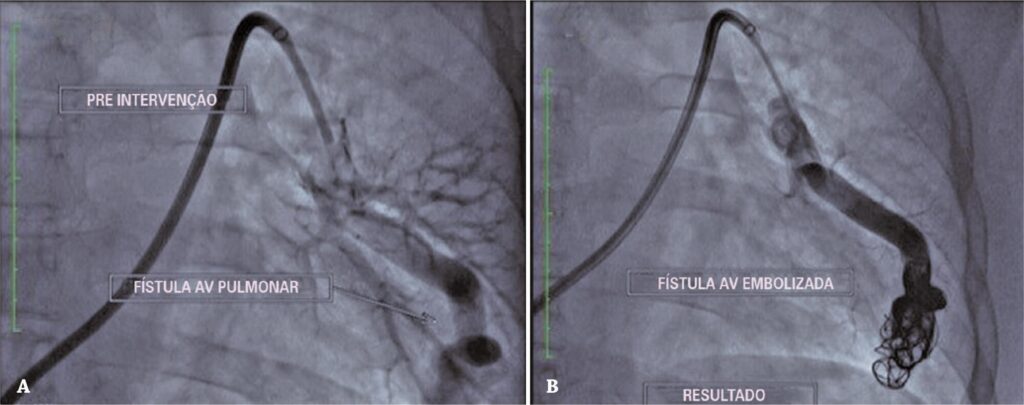

Figura 1

Fístula arteriovenosa pré (A) e pós-embolização (B).